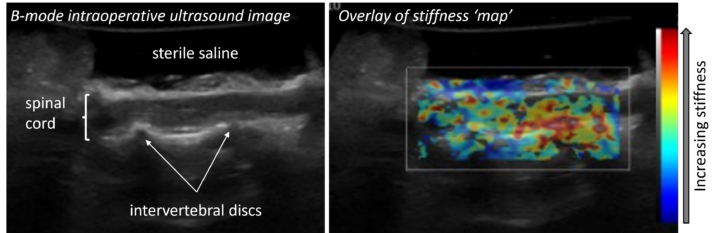

Intraoperative use of ultrasound (Figure 1) has been reported during spinal surgery for intervertebral disc extrusions, protrusions and spinal tumours in dogs (Kramer et al., 2011; Nanai et al., 2007). The approach (eg hemilaminectomy window) is filled with sterile saline and the ultrasound probe covered with a sterile sleeve, allowing images of the spinal cord to be obtained. This adjunctive imaging can assist in more complete decompression or resection.

Ultrasound elastography has also been used intraoperatively in dogs undergoing hemilaminectomy for intervertebral disc extrusion. This technique enables the non-invasive measurement of the elasticity (or stiffness) of the spinal cord, which could be correlated to the clinical severity of the injury (Prager et al., 2020). There was a very preliminary suggestion from this study that paraplegic dogs with no deep pain sensation who did not recover ambulation had a stiffer site of injury compared to the surrounding spinal cord. All dogs that recovered had a less stiff site of injury. This is currently being explored further in a prospective study.